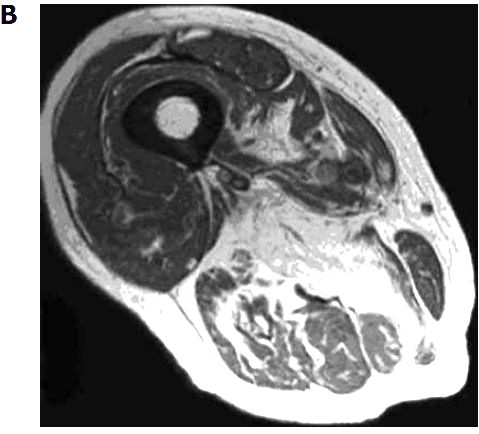

Figure 2

Magnetic resonance imaging of two different grades of fatty degeneration and atrophy involving thigh muscle in patients with vitamin D deficiency.

A Grade 1 (less than 30% of the volume of muscles involved);

B: Grade 2 (30%-60% of the volume of muscles compromised).

For illustration, Figure 2 shows MRI of two different grade of fatty atrophy involving thigh muscle in patients with vitamin D deficiency. The hypothesis that arose was that atrophy of skeletal muscle fibers and their replacement by fat tissue are the anatomic basis for the impairment in muscular performance described in older vitamin D-deficient people[4]. It may supposed that fatty substitution related to vitamin D deficiency may be the result of the lack of the known trophic effects of vitamin D on skeletal muscle cells[4]. If the thigh muscles are affected, the lack of enough muscular bulk may hamper balance and gait. Clinical scores were concordant with this observation. Concerning technical MRI protocols we suppose that a standard, patient-friendly protocol, including T1 and T2 weighted sequences may be sufficient for the follow-up of elderly people with potential vitamin D deficiency. In another study of 366 older patients receiving MRI of one shoulder for the investigation of potential rotator cuff injury, a correlation between higher fatty infiltration of rotator cuff muscles and lower serum levels of 25D was reported[22]. After multivariate linear regression analysis, this association remained statistically significant in two muscle groups (i.e., supraspinatus and infraspinatus muscles) but only among those whose MRI also demonstrated a full-thickness rotator cuff tear (228 patients).